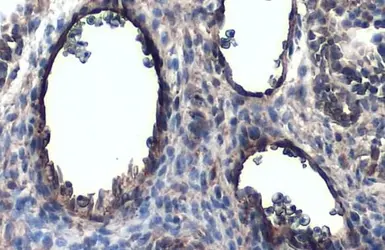

CD31 antibody detects CD31 protein at cell membrane and cytoplasm by immunohistochemical analysis.

Sample: Paraffin-embedded mouse placenta.

CD31 stained by CD31 antibody (GTX130274) diluted at 1:1000.

Antigen Retrieval: Citrate buffer, pH 6.0, 15 min